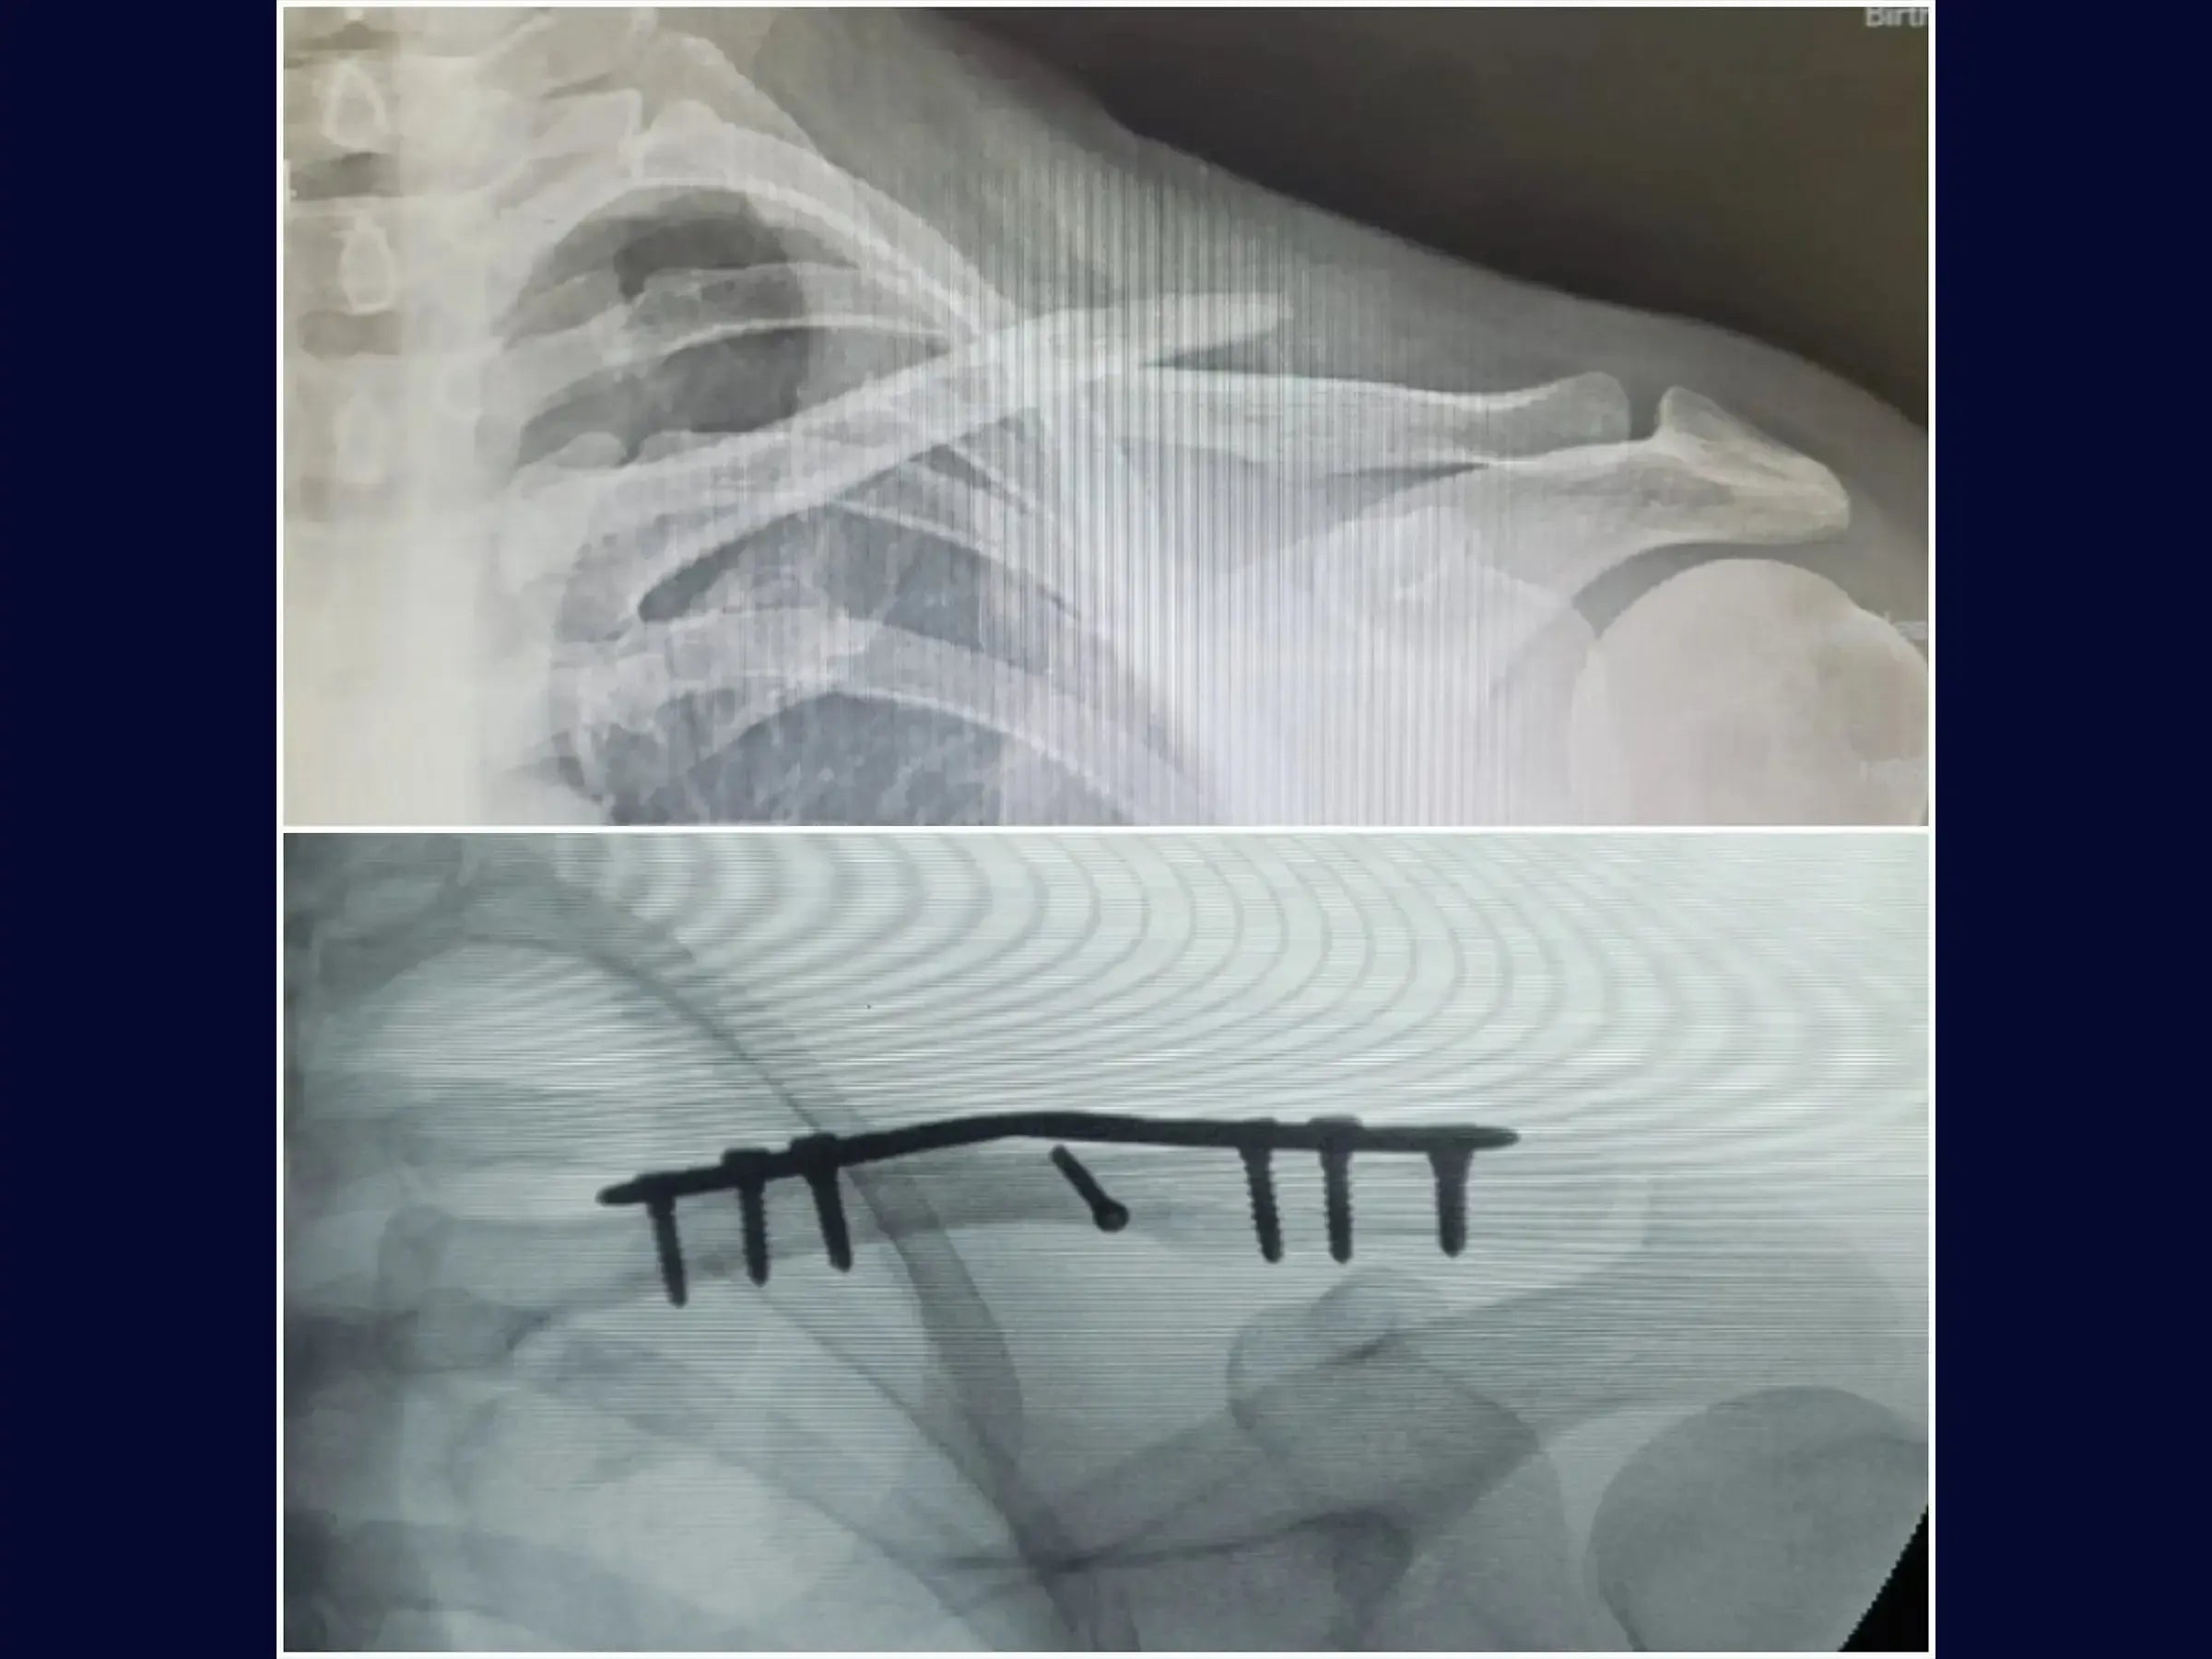

Domine o tratamento de fraturas desviadas do terço médio da clavícula. Este treinamento oferece uma imersão técnica na osteossíntese com placa em ponte via acesso minimamente invasivo, destacando a preservação tecidual e o resultado estético favorável.

- Tratamento cirúrgico de fraturas desviadas do terço médio da clavícula com sofrimento de pele.

- Técnica de fixação em ponte com placa.

- Abordagem minimamente invasiva com dois portais.

- Redução Precisa com Pinça Dedicada: Metodologia de identificação e redução da fratura através de mini acesso lateral com pinça específica, facilitando a manipulação.

- Fixação Biomecanicamente Eficaz: Estratégias para inserção de parafuso interfragmentar em traços oblíquos e sequência de fixação com parafusos nos terços lateral e proximal da clavícula.